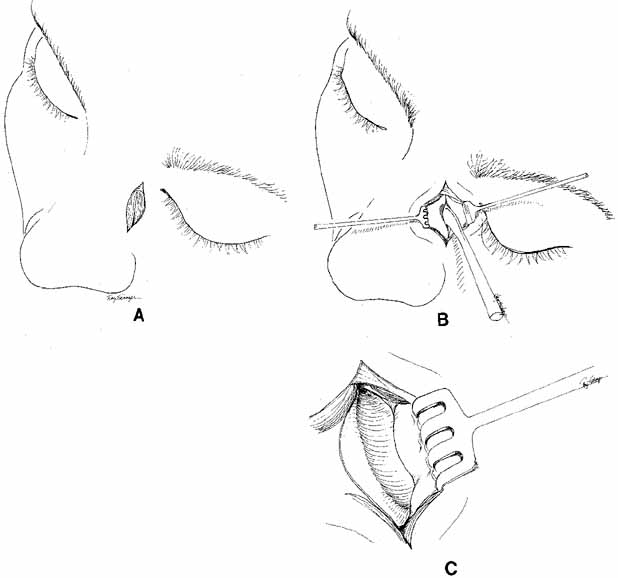

Fig. 27 A and B. Monocanalicular stent with collarette. Note placement when appropriately

seated in puncta.

Fig. 27 A and B. Monocanalicular stent with collarette. Note placement when appropriately

seated in puncta.

FIXATION OF TUBING. Monocanalicular stents are easy to fix in place. Once placed, the tubing

has a collarette with a punctal anchor on the proximal end that nicely

seats itself in the puncta similar to a punctal plug. The collarette

has two components: a flat surface that lies on the lid margin, and

a small bump under the plate, that anchors into the puncta (Fig. 27A and 27B). The colarette comes in two sizes, 3 mm and 4 mm. We prefer the

smaller 3-mm–sized stents for use in infants and toddlers.72 For adolescents and adults, we recommend using the 4-mm–sized

tubes. The stent is placed over a Ritleng probe as previously described. Of

note, the difficulty with these tubes is not fixation but rather

the passage through the nasolacrimal system. Once the stent is in

place, a small punctal plug seating device is inserted into a small

hole in the anchoring plate. The surgeon can facilitate seating the stent

by simultaneously pulling the distal prolene potion and pushing the

anchor with the seating device. A small pop is felt when then anchor

locks into the punctum. If the punctal plug seating device is not available, a

number 0000 Bowman probe or a fine tip punctal dilator can be

used instead. |